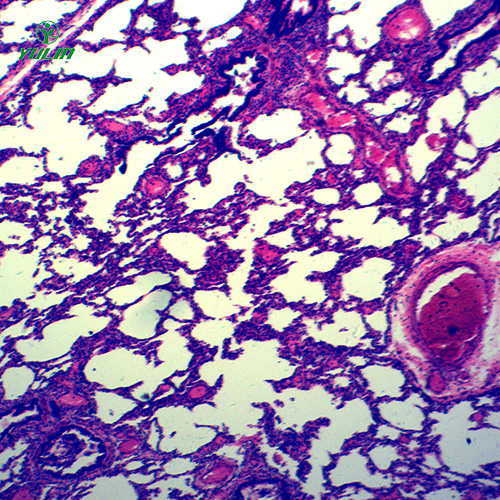

广东循环系统浸制标本